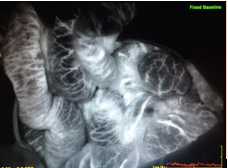

Fluorescence angiography (FA) utilizing indocyanine green (ICG) has been used for decades to assist with ophthalmic operations¹. Recently, its use has become more common in the management of myocutaneous flaps, ostomy and intestinal anastomoses. The use of ICG dye angiography in determining the viability of bowel and how it affects the surgeon’s management is relatively unknown. Below is a case of a 63-year-old male who presented in the intensive care unit (ICU) with an acute abdomen concerning for ischemic bowel. Fluorescence angiography was a key adjunct for the operative decision making for this patient.Published